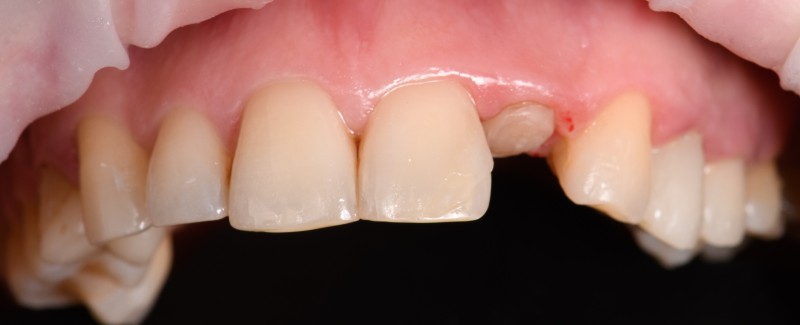

Установка керамической коронки

Протезирование зуба 12 керамической коронкой @po_makedonsky спасибо за работу

Доктор: Капитонова Екатерина Андреевна